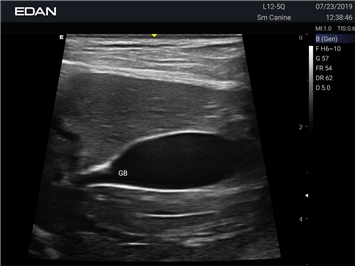

Ветеринарный ультразвук одним нажатием. Система Acclarix AX2 VET разработана с целью обеспечить бескомпромиссную производительность по доступной цене. Наличие уникальных двойных аккумуляторов в легком корпусе массой 4,5 кг из магниевого сплава позволяет системе Acclarix AX2 VET удовлетворять все потребности ветеринарных исследований, сохранив низкую стоимость.

EDAN Acclarix AX2 VET представляет собой специализированную ветеринарную ультразвуковую систему, сочетающую высокую производительность с доступной ценой. Благодаря продуманной конструкции и передовым технологиям, система обеспечивает качественную диагностику животных различных видов.

B-режим, Двухмерное сканирование:

Да

• Предустановленные протоколы для различных видов животных